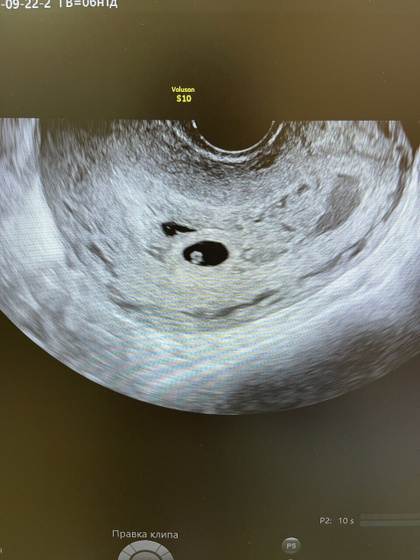

Ходила на узи, аппарат очень хороший, врач тоже со стажем, но смотрит и понять не может- что это за второе образование рядом с плодным яйцом?

Я на узи его смотрела тоже, оно прям круглое тоже, но внутри пусто, какие-то небольшие вкраплены и полосочки??♀️

Сказала через неделю на контрольное идти, вроде на ПЯ не похоже, в общем глазами хлопает и сама понять не может?

Гематома, отслойка так выглядит. Странно, что хороший врач этого не знает.

Отслойка так может выглядеть

Отслойка чего? Там нечему отслаиваться еще. Да, скорее всего пустая оболочка… у меня подобное в 7 недель было. Сказали поздняя овуляция вторая и вот это вот.

Отслойка справа, более бледная есть и больше размером) может конечно вторая отслойка?

Того… Отслойка плодного яйца!!! Вы так уверено говорите конечно ??

Да вижу. Сама с 7 ой недели лежала с гематомами двумя. К 11 ой только видео перестало быть на УЗИ.